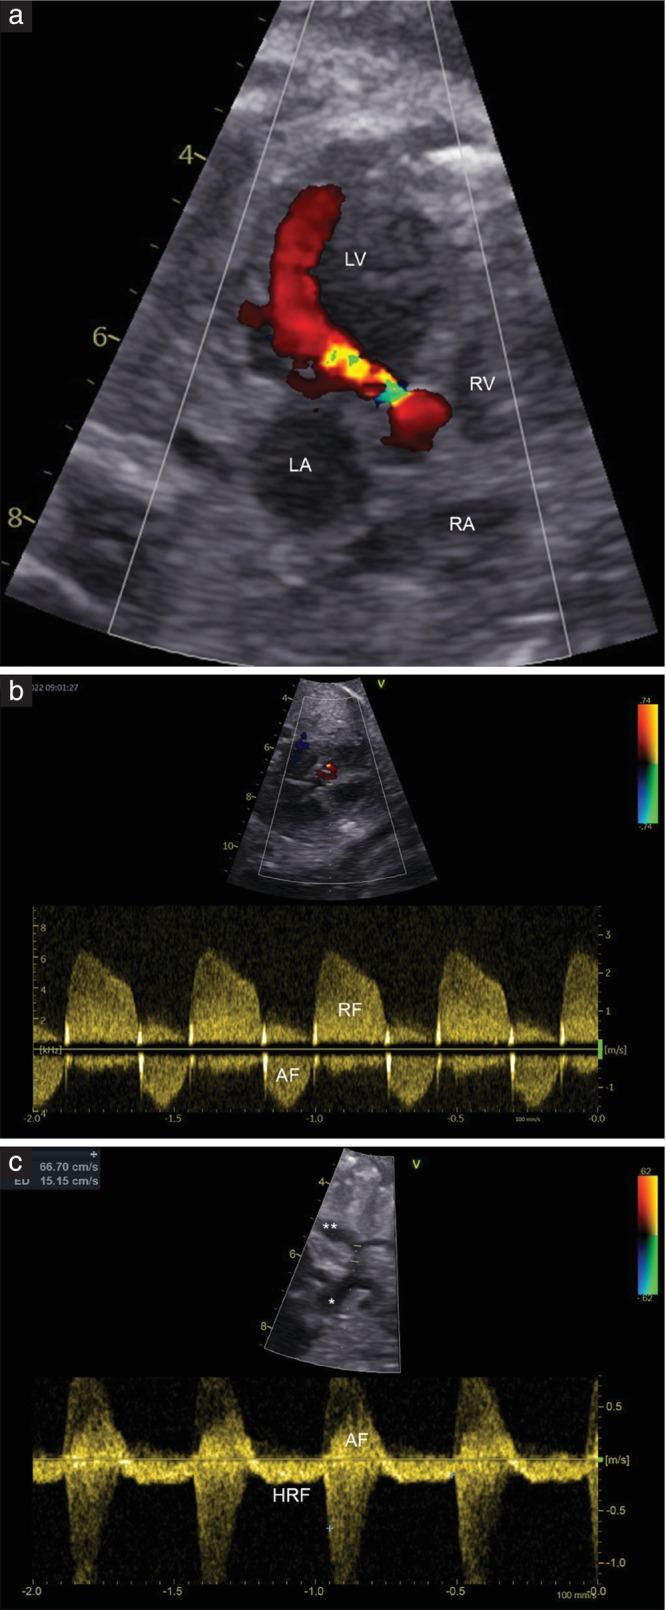

To analyze the prevalence and severity of fetal aortic regurgitation (AR) after undergoing successful fetal aortic valvuloplasty (FAV) and to evaluate its effects on fetal circulation and left ventricular (LV) growth.

This was a retrospective review of all fetuses with critical aortic stenosis who underwent successful FAV at our center between 2010 and 2024 for whom postnatal echocardiograms were available in digital format. Fetal and postnatal echocardiographic examinations were analyzed for ventricular and valvular dimensions and characteristics, and Z-scores were calculated for middle cerebral artery (MCA) pulsatility index (PI), umbilical artery (UA) PI and cerebroplacental ratio. AR severity was classified into no/mild AR or significant (moderate/severe) AR. The balloon-to-aortic valve ratio (BVR) was calculated as the ratio between the maximum actual balloon diameter and the aortic valve (AV) annulus diameter. The primary endpoints of this study were the prevalence, severity and risk factors for fetal AR following successful FAV.

Ninety-nine fetuses who underwent successful FAV were included. Immediate post-FAV echocardiograms showed that 87% of fetuses developed some degree of AR, including 45% of all fetuses with significant AR. BVR was significantly higher in fetuses with significant AR compared to those with no/mild AR (mean, 1.09 (95% CI, 1.06-1.12) vs 1.02 (95% CI, 0.99-1.04); P < 0.001). In a subgroup of 66/99 fetuses with available postnatal echocardiograms, the prevalence of AR decreased significantly from 86% before birth to 58% after birth (P < 0.001), with the proportion of fetuses with significant AR reducing from 47% before birth to 17% after birth (P < 0.001). In the overall cohort of fetuses, AV maximum velocity (Vmax) increased significantly from post-FAV to after birth (mean, 1.93 (95% CI, 1.75-2.11) m/s vs 3.21 (95% CI, 2.89-3.55) m/s; P < 0.001), regardless of AR severity, but Vmax after birth was lower in the significant-AR group compared with the no/mild-AR group (mean, 2.85 m/s vs 3.55 m/s; P = 0.020). Fetuses with significant AR exhibited higher relative LV length increases from immediately post-FAV to after birth than did those with no/mild AR (25% (95% CI, 16-33%) vs 14% (95% CI, 6-21%); P = 0.044), although there was no significant difference in mean LV length Z-score after birth between the two groups. FAV led to significant short-term increases in MCA-PI and UA-PI Z-scores, with greater increases observed in fetuses with significant AR.

FAV is associated with a high prevalence of fetal AR, which lessens in severity over the course of gestation. Significant fetal AR had the largest association with greater BVR and had significant impact on fetal hemodynamics. © 2025 The Author(s). Ultrasound in Obstetrics & Gynecology published by John Wiley & Sons Ltd on behalf of International Society of Ultrasound in Obstetrics and Gynecology.